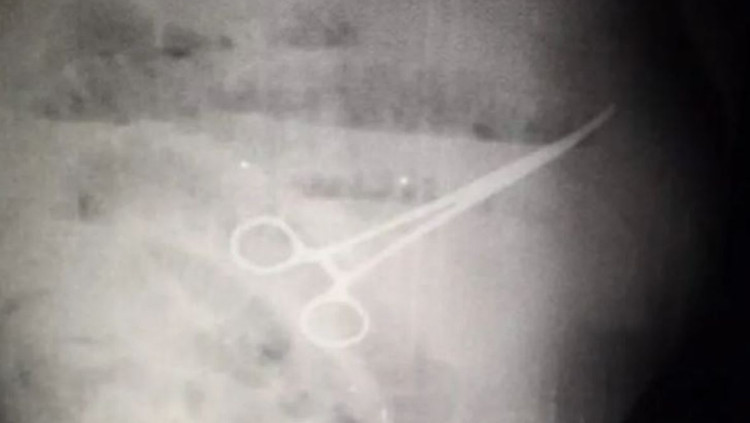

הרופאים אמנם הצליחו בניתוח הקיבה, אך גרמו למותו של המטופל בגלל חפץ ששכחו בבטנו